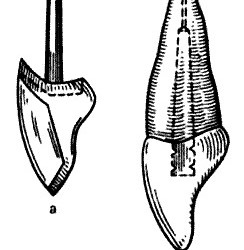

Жевательная проба. Критерий оценки эффективности работы жевательного аппарата, которую определяют по 3 показателям: жевательная эффективность, жевательный эффект и жевательная способность. Тестовым материалом для жевательной пробы могут служить пищевые продукты (орехи, морковь, хлеб) и искусственно созданные (20% желатина, отвержденная в 4% формалине, ортосил, другие пластмассы). Обязательным условием для воспроизводимости результатов пробы […]